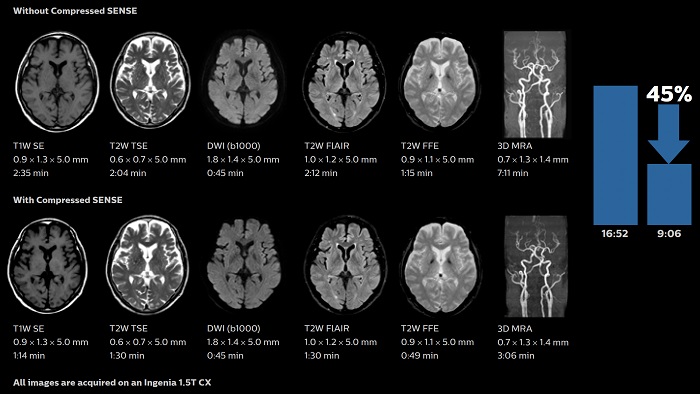

Compressed SENSE

Krótszy czas i wysoka jakość obrazowania